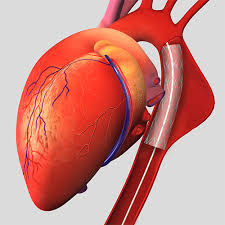

Overview

Package includes:

Days in hospital : 7 to 8 Days (For patient and one attendant)

Days in hotel : 12 Days (For patient and one attendant)

Room type in hospital : Shared

Room type in hotel : Private

Hotel category: Standard

Value added benefits of the CABG:

Ø Doctor consultation charges

Ø Lab tests and diagnostic charges

Ø Room charges inside hospital during the procedure

Ø Surgeon Fee

Ø Nursing charges

Ø Hospital surgery suite charges

Ø Anesthesia charges

Ø Routine medicines and routine consumables (bandages, dressings etc.)

Ø Food and Beverages inside hospital stay for patient and one attendant.

Extra benefits:

ü Interpreter

ü Visa assistance

Ø Site tourism of the city

Ø Follow up with the doctor

Ø Airport pick up and drop

Ø Free online consultation with the doctor

Ø Priority appointments with the doctor

Ø Room upgrade from sharing to private